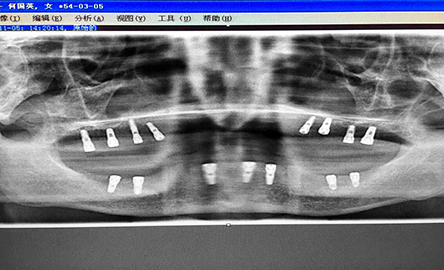

在经过严谨的种植方案分析后,根据何女士的口腔情况和要求,周医生为其制定了固定式全口种植方案。由于骨量严重不足,在种植前周医生首先为何女士进行了植骨手术提高骨量,随后在上颌种上8颗种植体、下颌种植7颗种植体,全口仅通过15颗种植体,便轻松实现了全口牙齿重建的技术突破。

种植后全景片